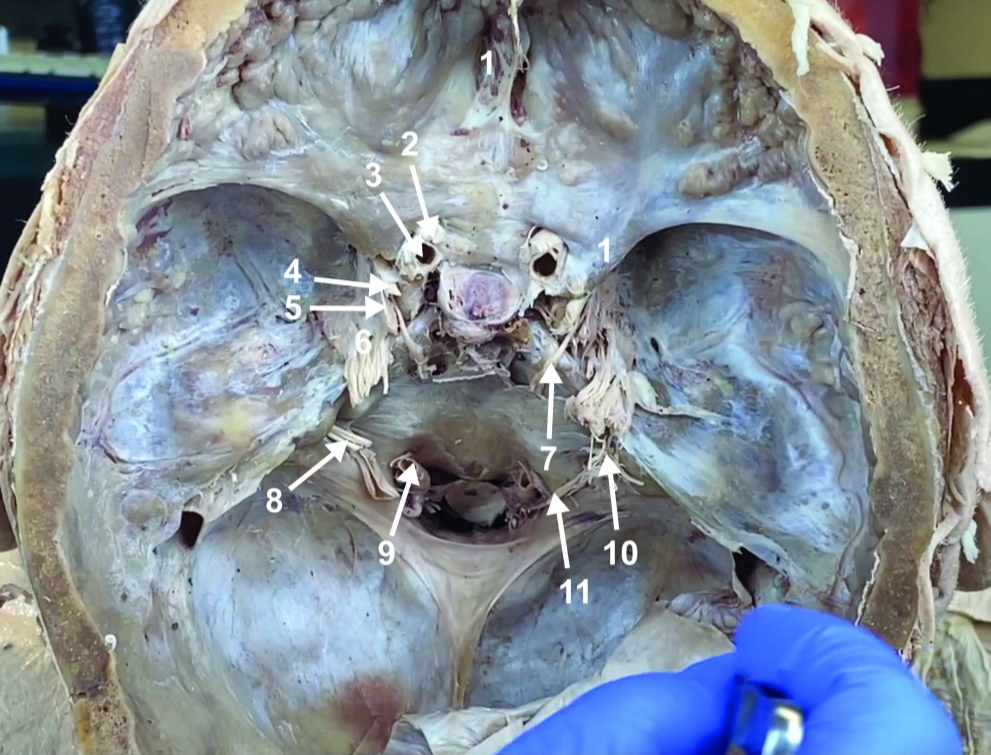

Foramen magnum

ID structure

Foramen ovale

ID structure

Foramen spinosum

ID structure

Cribiform plate

ID structure

Optic n. (CN II)

ID structure

Internal carotid a. (ICA)

ID structure

Occulomotor n. (CN III)

ID structure

Trochlear n. (CN IV)

ID structure

Trigeminal n. (CN V)

ID structure

Abducent n. (CN VI)

ID structure

Facial and vestibulocochlear n. (CN VII and VIII)

ID structure

Vertebral a.

ID structure

Glossopharyngeal and vagus n. (CN IX and X)

ID structure

Root of spinal accessory n. (root of CN XI)

ID structure

Ophthalmic division of CN V (CN V1)

ID structure

Maxillary division of CN V (CN V2)

ID structure

Mandibular division of CN V (CN V3)

ID structure

Foramen rotundum

ID structure

Foramen ovale

ID structure

Trochlear n. (CN IV)

ID structure

Abducent n. (CN VI)

ID structure